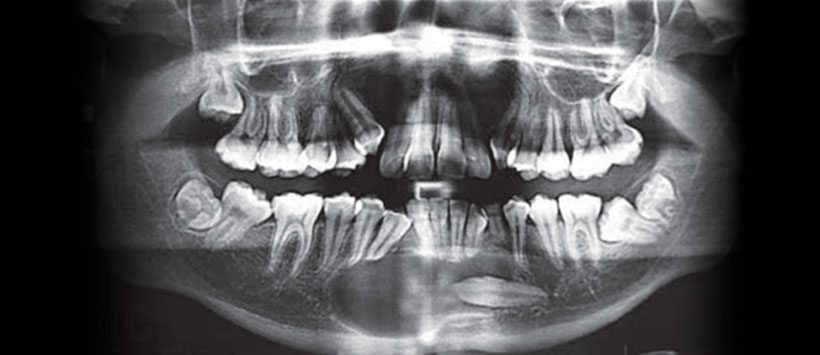

Se solicita al paciente ortopantomografía en donde se observa una imagen radiolúcida de bordes bien delimitados, unilocular, misma que rodea a un órgano dental incluido correspondiente a canino inferior izquierdo permanente, presenta desplazamiento radicular de canino inferior derecho, borde mandibular íntegro (Figura 1)